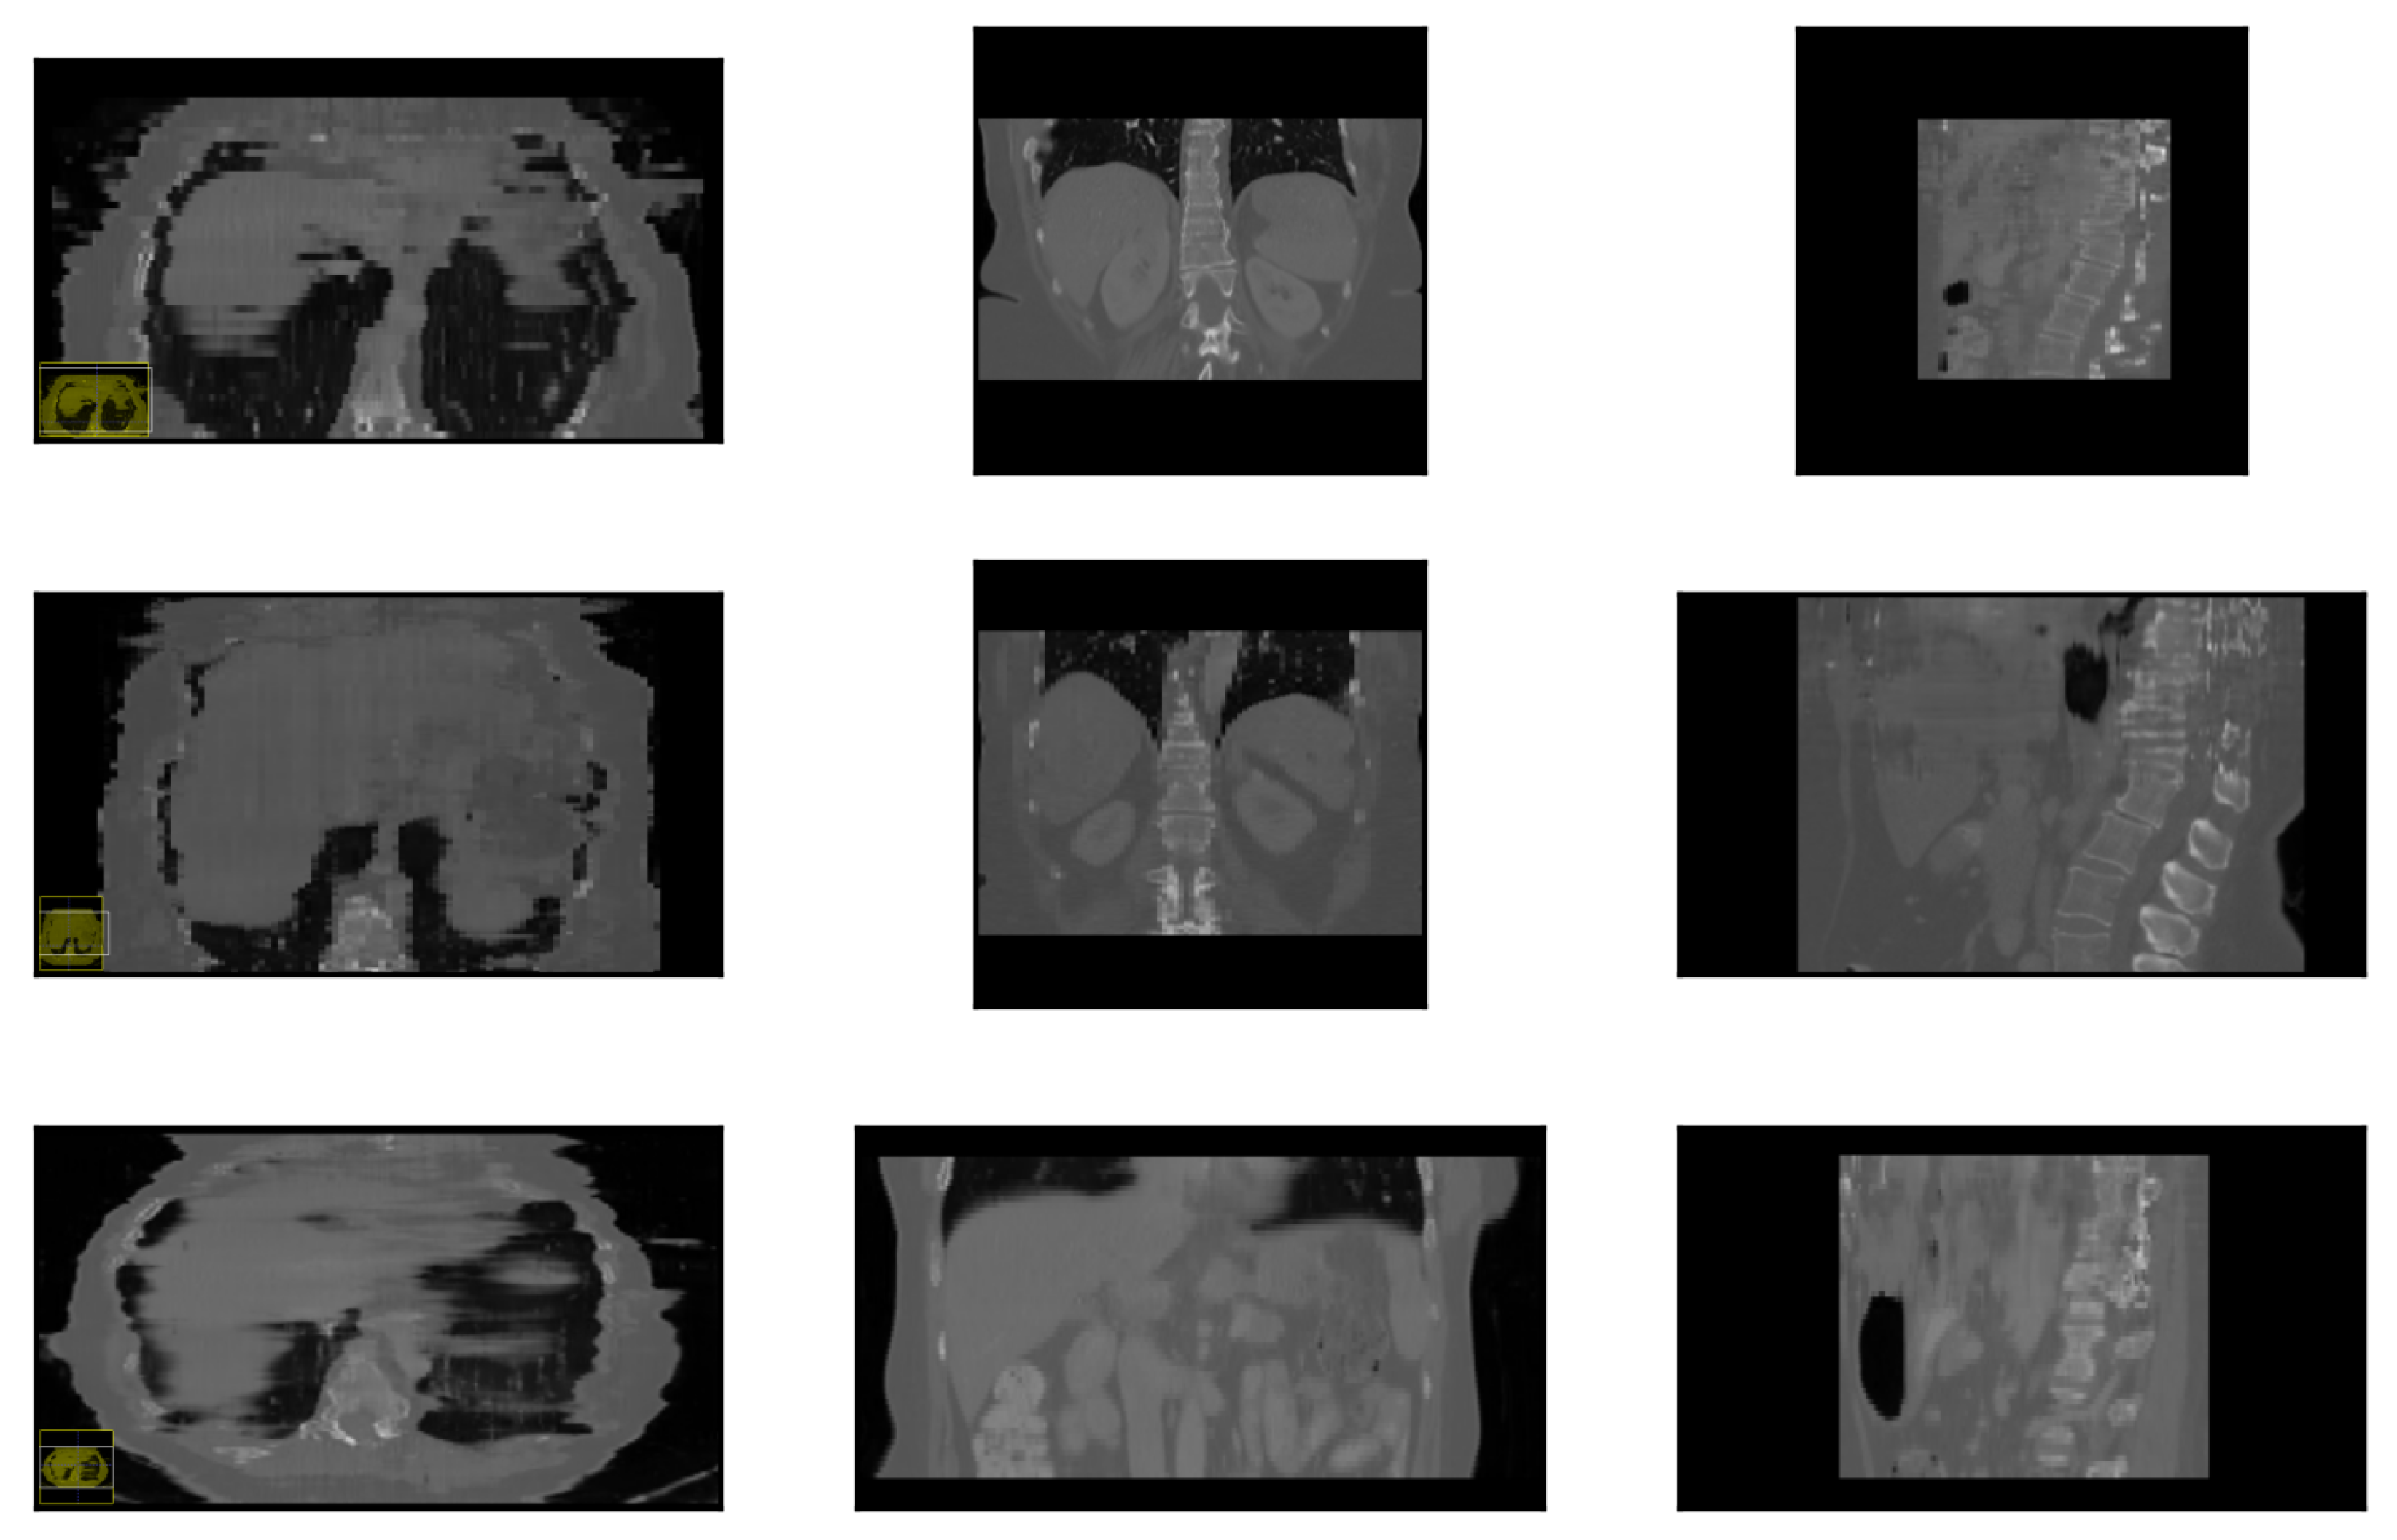

2. Materials and Methods

2.2. Proposed Method

3. Results